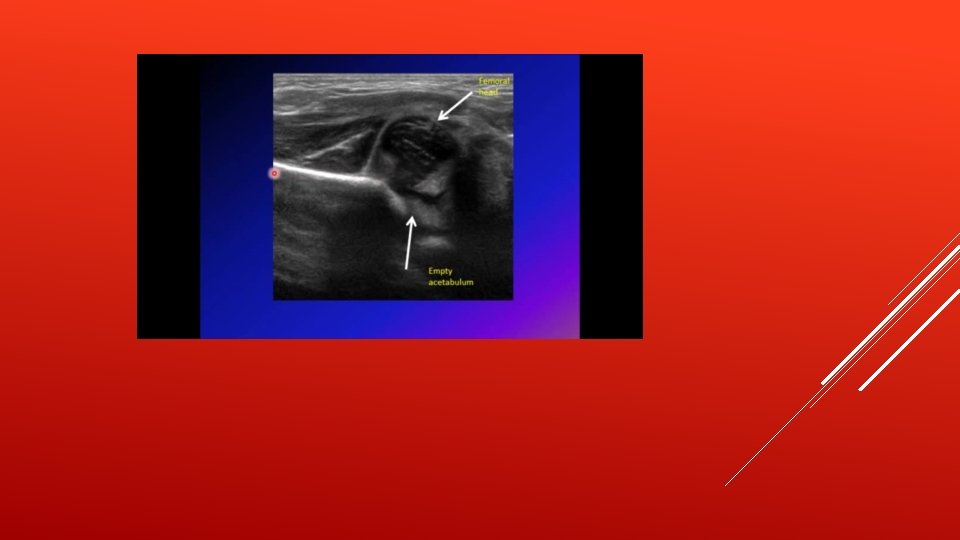

PEDIATRIC HIP - The hip is a deep seated joint and it’s the largest ball and socket joint formed by the acetabulum and femur head. - The acetabulum is the cup-shaped socket on the lateral aspect of the pelvis and it is formed by the ilium, ischium and pubis. - The margin of the acetabulum is deficient inferiorly. An additional fibrocartilaginous margin of the acetabulum is referred to as the acetabular labrum. The labrum functions to deepen the acetabulum, thus holding the femoral head more securely. - At birth the femoral head is less than 50% covered by the acetabulum, and the acetabulum is at its most shallowness and most laxity in order to maximize the hip ROM(range of motion) - After several weeks, the acetabular cartilage starts to develop faster than the femoral head, which allows for more coverage in a normal hip, the ball of the femur fits firmly into the socket - Hip develops after 12 wks of gestation

● Pathology: a. The acetabulum is shallow (shaped like a saucer instead of a cup). b. The femoral head gets dislocated. c. The capsule is stretched and the ligamentum teres becomes elongated and hypertrophied. ● Classification: a. Dysplasia b. Subluxation – Incomplete contact between the articular surfaces of the femoral head and acetabulum. c. Dislocation – Complete loss of contact. d. Instability – Ability to subluxate or dislocate the hip with passive manipulation e. In other words ■ Type 1 → acetabular dysplasia ■ Type 2 → acetabular dysplasia +Subluxation ■ Type 3 → frank dislocation